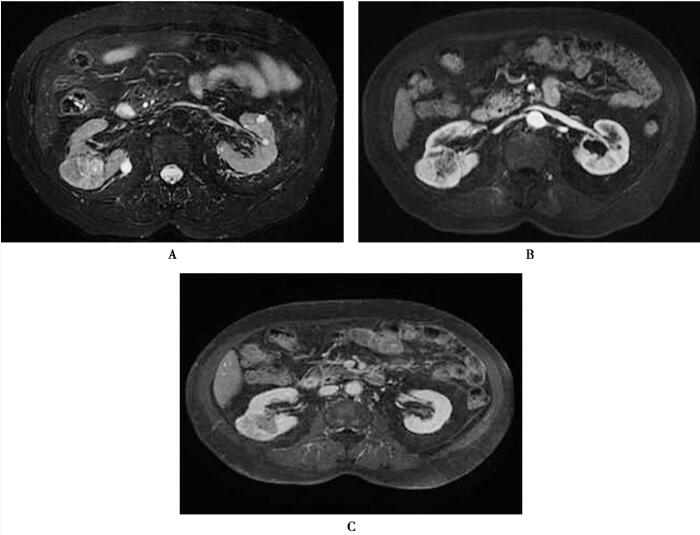

图1右肾透明细胞癌

在体轴横断位T2WI+FS图像上(A),显示右肾肿块稍高信号,其内部可见点片状更高信号,肿块由低信号包围,增强扫描动脉期(B)肿块显著不均匀强化,延迟期增强扫描图像(C)上肿块呈低信号,提示对比剂快速流出